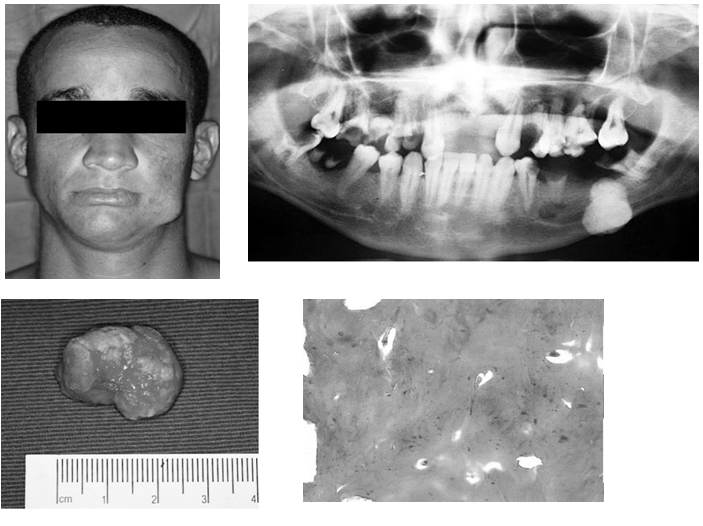

Osteoid Osteoma of the Mandible Clinical and Histological Findings Osteoma Oral Tratamiento La tomografía computarizada ayuda a delimitar el tamaño del tumor y su relación con las estructuras adyacentes.1,2,5 histológicamente. El presente estudio reporta el caso de un osteoma periférico aislado en un paciente de sexo masculino, de 30 años, localizado en la región del ángulo mandibular izquierdo. Three cases were managed through extra oral submandibular approach; El osteoma es una neoplasia. Osteoma Oral Tratamiento.

PDF PERIPHERAL OSTEOMA The Ramus of Mandible Report of Case Osteoma Oral Tratamiento El presente estudio reporta el caso de un osteoma periférico aislado en un paciente de sexo masculino, de 30 años, localizado en la región del ángulo mandibular izquierdo. El osteoma es una lesión osteogénica caracterizada por la proliferación de tejido óseo compacto o esponjoso. El osteoma es una neoplasia benigna osteogénica compuesta de tejido óseo maduro compacto o esponjoso bien. Osteoma Oral Tratamiento.